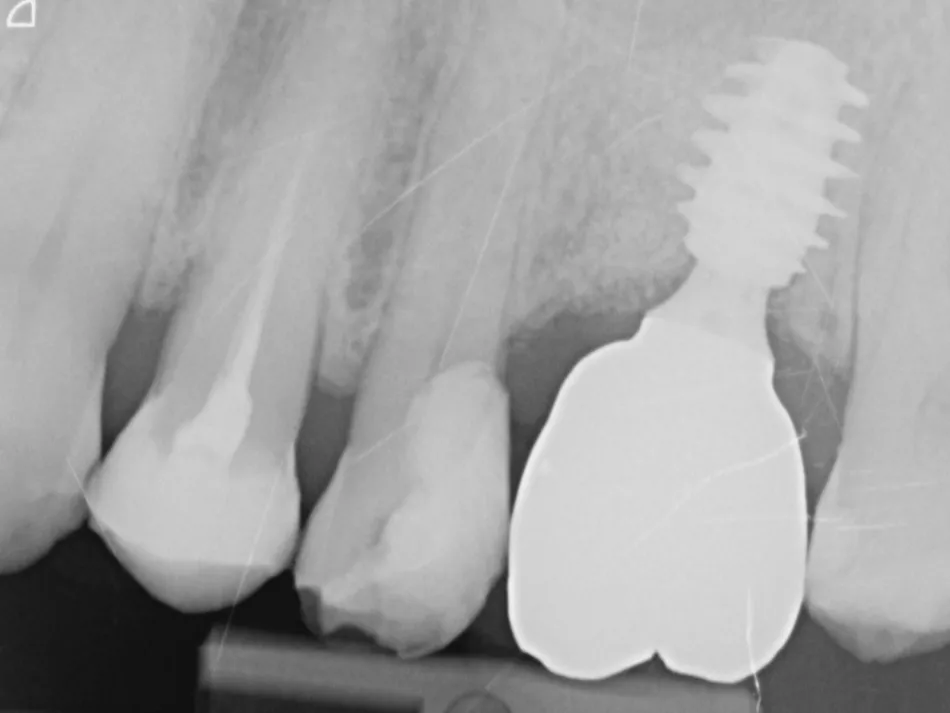

10a. 10b. 10c. 3D scans and radiograph control of the implantplacement.

10a

10b

10c